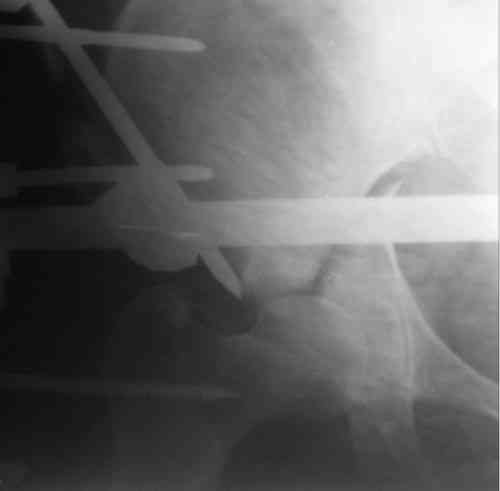

Пациентка 38 лет. В результате ДТП 02.09.06 получила поперечный перелом правой вертлужной впадины, центральный вывих правого бедра, разрыв правого крестцово-подвздошного сустава.

В одной из районных больниц вывих устранен, наложена система вытяжения по оси бедра и за вертельную область. Спустя 2 недели выполнен ВЧКО модулем "таз-бедро". Учитывая возраст пациентки и остаточный диастаз в области свода вертлужной впадины предполагается демонтаж аппарата, открытая репозиция и внутренний МОС вертлужной впадины через внутритазовый доступ.

На показанных снимках повреждение правого КПС не очень заметно...

У меня создалось впечатление( одна из РГ), что участок суставной поверхности нагрузочной зоны вертлужной впадины вдавлен( постарайтесь сделать КТ). Если это подтвердиться, то из внутритазового доступа отрепонировать будет невозможно.